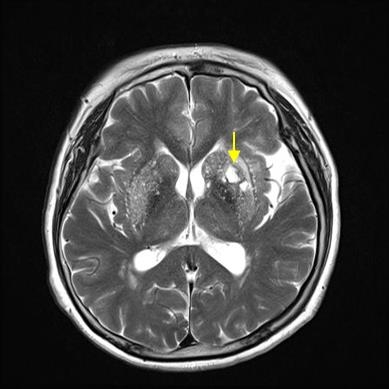

뇌경색은 병에 걸려 후 얼마나 빨리 치료를 착수하는지에 따라 병의 증세가 결심되기도 합니다. 증상이 발생하면 아주많이 빨리 병원을 가서 초급성기 치료를 받아야합니다. 급성기 치료 후에는 이유가 되는 것에 따라 재발 방지를 위한 치료를 하게 되며 후유증에 대한 재활치료도 가능한 한 빨리 실행하는는게게 좋바람직해요. 증상이 처음 나타난 후 4~5시간이 경과하지 않으신다면 주사 제제를 통한 혈전용해술을 시도해 볼 수 있어요. 그리고 24시간이 경과하지 않았고 대뇌혈관이 막힌 것을 확인했으면 막힌 혈관에 대하여서 스텐트 투여술과 같은 기계적 재개통술을 시도할 수 있습니다.